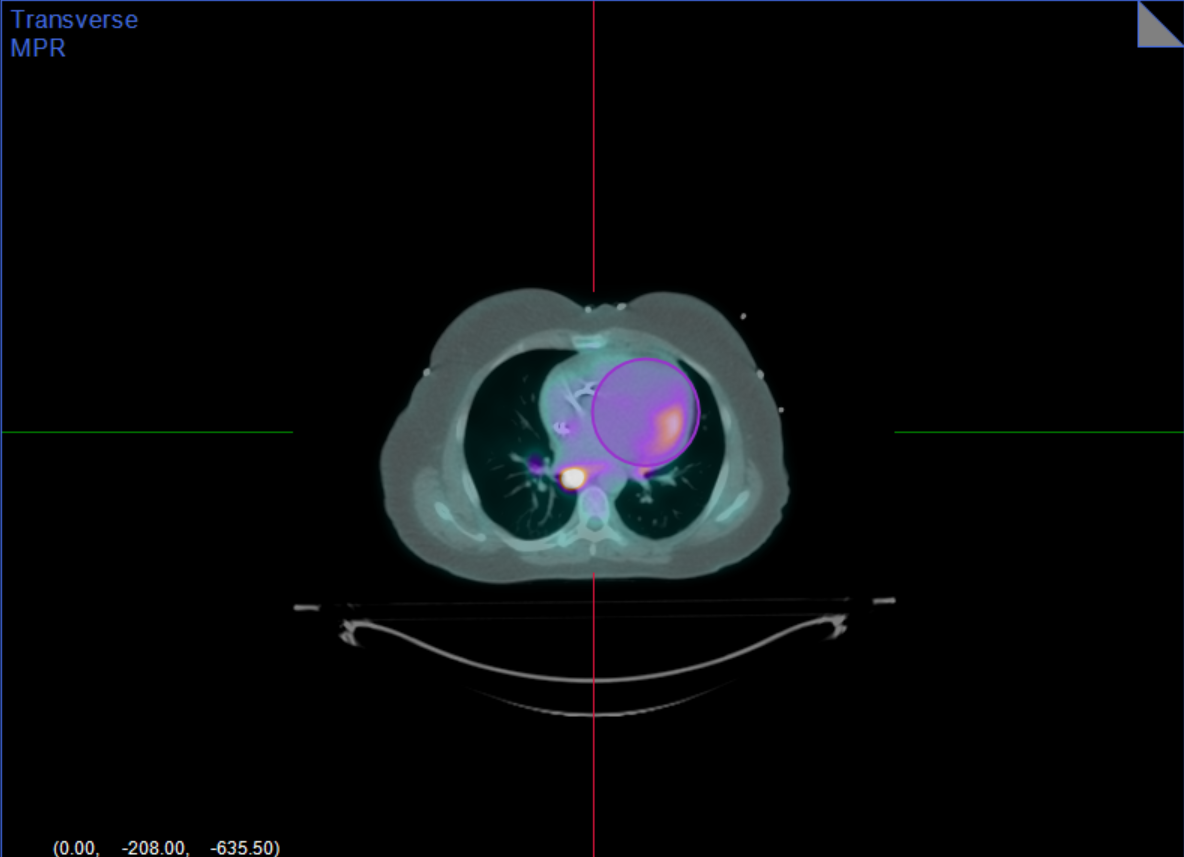

Diagnostic performance of ¹⁸F-flurpiridaz PET myocardial perfusion imaging with total perfusion deficit quantification

Summary